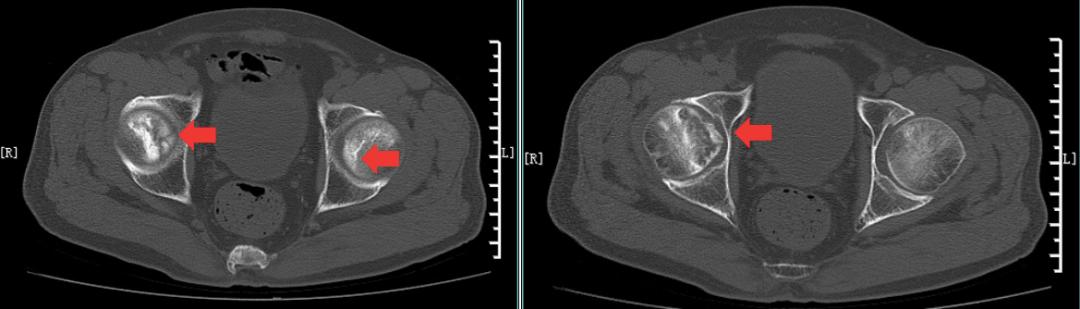

股骨头CT:右侧股骨头变形、塌陷,右侧股骨头骨质内见囊性骨吸收破坏区,部分边缘硬化,左侧股骨头局部密度增高,余双侧髋臼骨质增生,关节在位,关节间隙未见明显异常(图4)。检查结论:右股骨头坏死改变,左股骨头局部密度增高,建议进一步MRI检查。

图4 股骨头CT